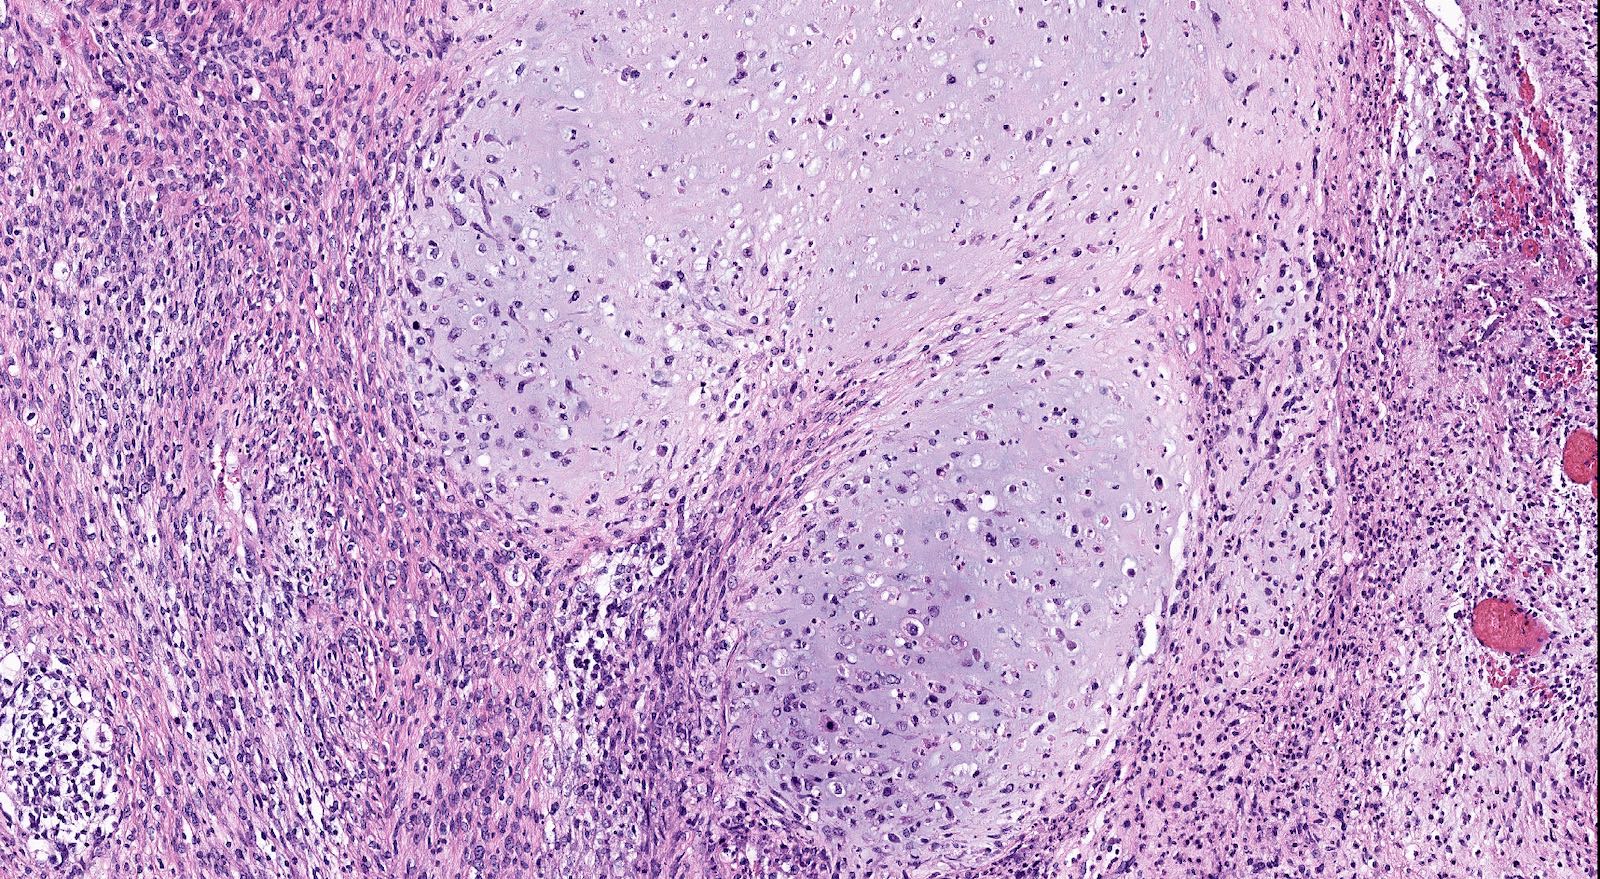

Microscopic (histologic) description

- Biphasic tumor with carcinomatous and sarcomatous elements, both high grade (Int J Gynecol Pathol 1990;9:1)

- Carcinomatous and sarcomatous components are juxtaposed

- Carcinomatous elements:

- Often high grade endometrioid or serous carcinoma, frequently admixed

- More uncommonly clear cell carcinoma

- 50 - 75% of cases have serous or mixed serous and high grade endometrioid carcinoma (Am J Surg Pathol 2007;31:1653)

- Hybrid morphology between endometrioid and serous carcinoma is frequent, as is undifferentiated carcinoma (Mod Pathol 2010;23:781)

- Other components that can be rarely found are squamous, mucinous and neuroendocrine

- Sarcomatous elements:

- Often spindle and pleomorphic

- 50% contain heterologous elements (most commonly rhabdomyosarcoma and chondrosarcoma) (Am J Surg Pathol 2007;31:1653)

- Osteosarcomatous, liposarcomatous and angiosarcomatous differentiation are less common (Semin Diagn Pathol 1988;5:199, Arch Pathol Lab Med 1991;115:583, Int J Gynecol Pathol 2017;36:140)

- Carcinomatous elements:

- Angiolymphatic invasion common, more commonly of the carcinomatous component

Microscopic (histologic) images